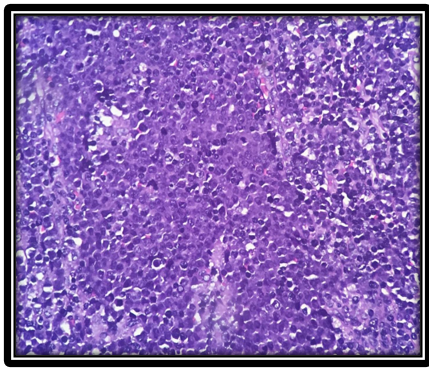

On histopathological evaluation, non-Hodgkin lymphoma without further subtyping was the most common diagnosis (33/48 = 68.75%). Among cases where subtyping was performed based on histomorphology, follicular lymphoma (3/48 = 6.25%) and diffuse large B-cell lymphoma (DLBCL) (3/48 = 6.25%) were equally common. Diagnostic frequencies are presented in Table 4. Representative histopathological images of DLBCL and follicular lymphoma are shown in Figure 1 and Figure 2, respectively.

Figure 1. Diffuse large B cell lymphoma (H and E, 400x)